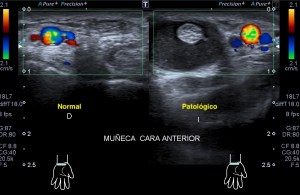

La radiografía revela aumento de las partes y se refrenda en la ecografía como puedes ver en la imagen aunque aún no hay afectación en el hueso en el caso que te presento hoy.

Ecografícamente y debido a su levedad, en el caso de hoy solo observamos cambios en las partes blandas de la cara lateral de la cabeza del quinto metatarsiano, este tejido se muestra heterogéneo, la cortical del hueso ligeramente prominente sin afectación de la misma.